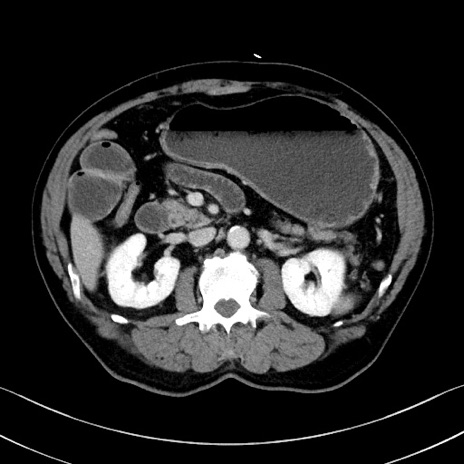

症例35(横断像)

【症例】70歳代 男性

【主訴】腹部膨満、嘔吐

【現病歴】昨日より腹部膨満感出現。本日増悪し、仙痛出現。嘔吐あり、受診。

【既往歴】糖尿病、胆摘後

【身体所見】BP 149/80mmHg、HR 74/min、BT 35.9℃、腹部:膨満、軟、圧痛なし。腸雑音減弱あり。上腹部正中切開瘢痕あり。

【データ】WBC 13500、CRP 1.72